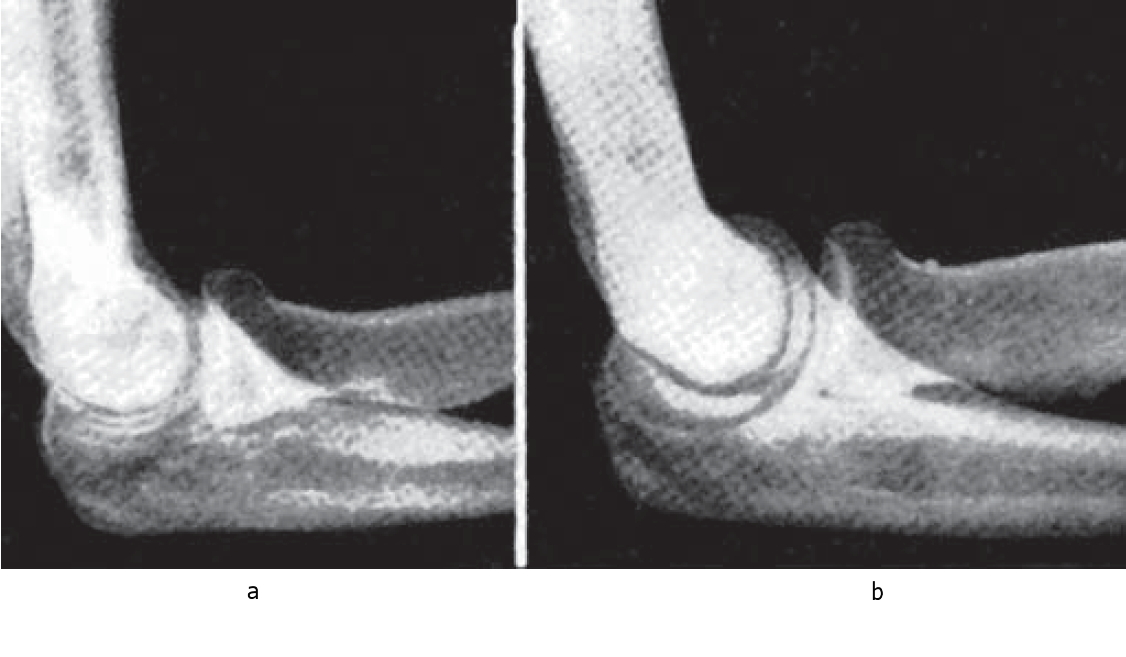

The effect of bone rest points (mutual bone slip limited protuberances) is shown depending on their isolation from corresponding contact surfaces on other bone or bones (Fig. 3). The form of rest points is also of great importance. In highly active joints they are smoothed, make a slight angle with the bone surface, promoting potential additional slip in case of mutual isolation of articulating bones. In inactive joints rest points are sharply precipitating over the bone surface. They simultaneously stop moving after contact with similar sharply formed contact surfaces.

Fig. 3. Intensity of olecranon and coronoid processes, depth of cubital fossa adequate and inadequate to “solid of rotation”, form of caput ulnae in highly active (a) and inactive (b) curbital articulations.